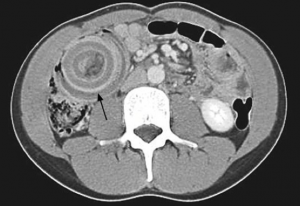

We're back with Part 2 on EBM updates concerning the imaging and management of adult appendicitis.

The emDOCs Podcast covers EBM Updates in the adult patient with appendicitis, specifically history and exam, lab testing, and diagnostic scoring systems.